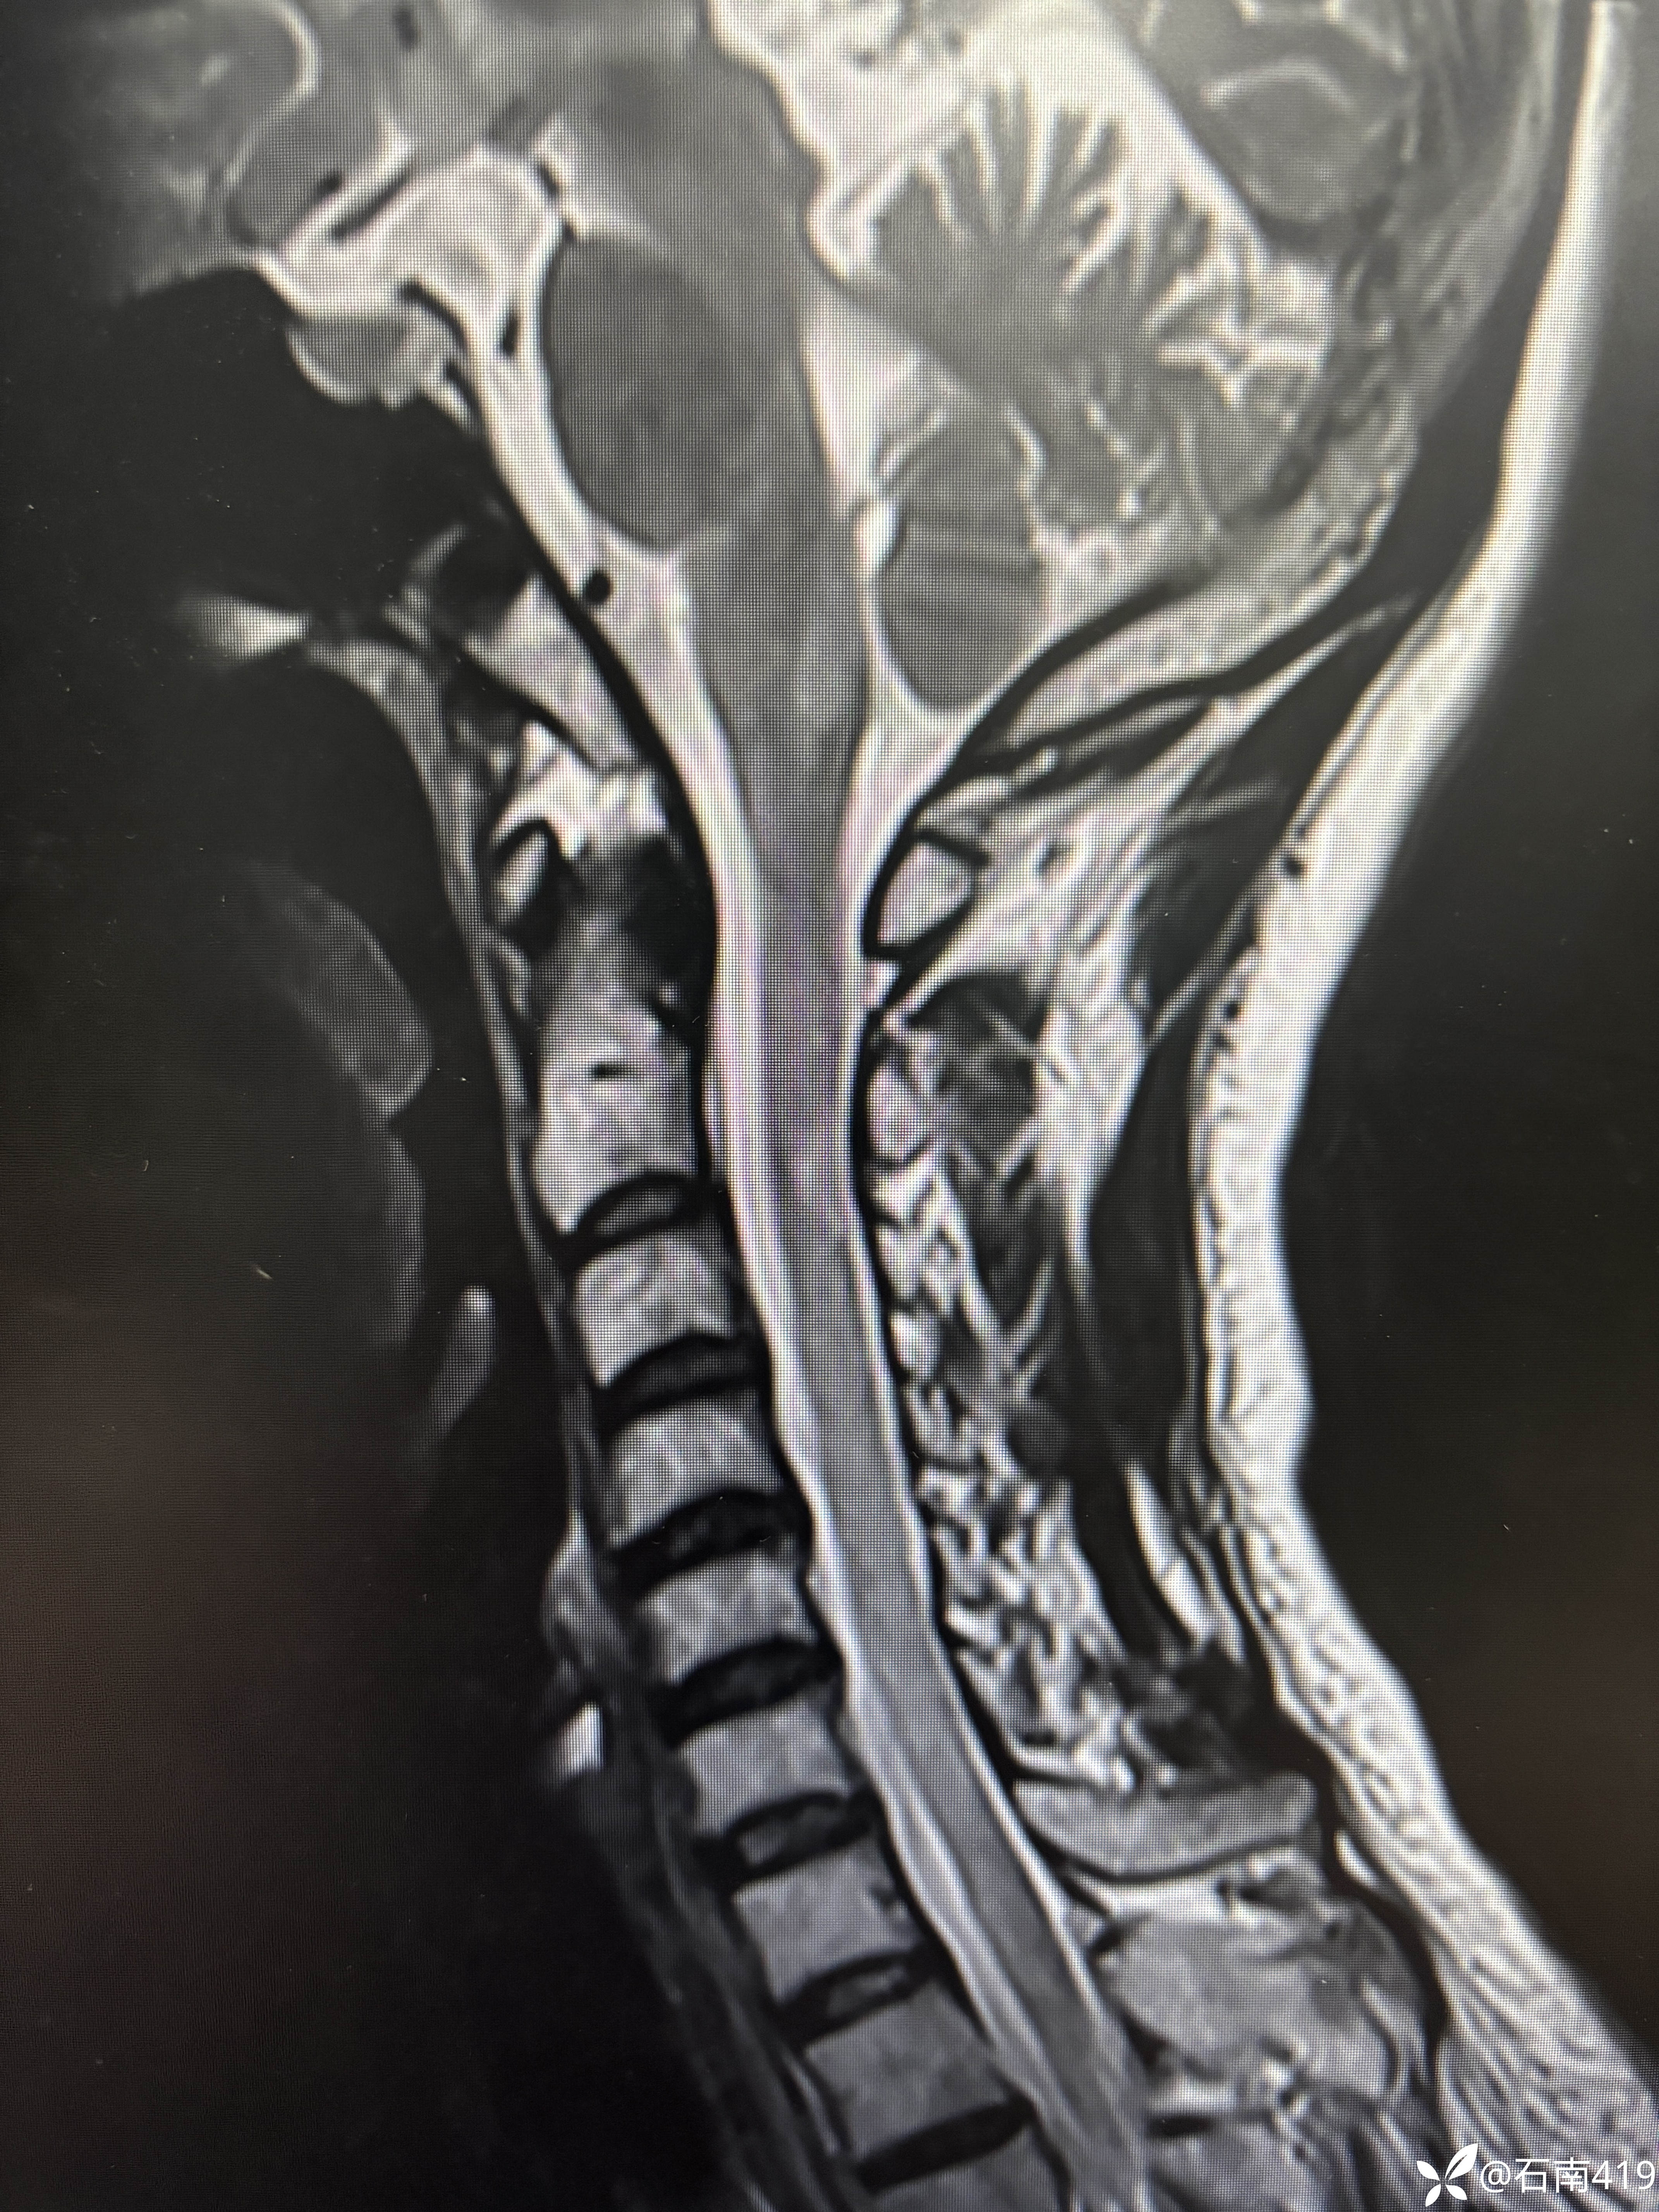

肢体无力半年,考虑什么?

患者,女,35岁,因“肢体无力半年”入院。

患者半年前无明显诱因出现左侧肢体无力,持续3天后自行好转。后出现行走后双下肢沉重无力,休息可缓解。1月前症状加重,上楼梯、蹲下起立困难,伴下肢肌肉酸胀,无皮疹,无二便改变,无晨轻暮重,至当地医院腰椎MR.I轻度退行性变,子“地奥司明、艾瑞昔步”口服,症状无改善。为求进一步诊治,拟“肢体无力”收治入院。

查体:神清,精神可,痉挛步态,言语清晰,对答切题,双眼眼球各向活动到边,双侧瞳孔等大等圆,直径3mm,对光灵敏,伸舌居中,双侧鼻唇沟对称,抬头肌力4级,双上肢肌力5级,右下肢肌力近端3+级,远端4级,左下肢肌力近端4级,远端5级,四肢腱反射亢进++++,双下肢肌张力增高,深浅感觉无增减。双侧指鼻不准,轮替慢,左侧明显,跟膝胫不准,闭目难立征阳性。霍夫曼征阴性,髌阵挛、踝阵挛阳性,双巴氏征阳性。

辅助检查:(2024-05-09,湖州市中心医院》腰椎MRI:腰椎轻度退行性变,胸11-腰2锥体许莫氏结节形成。